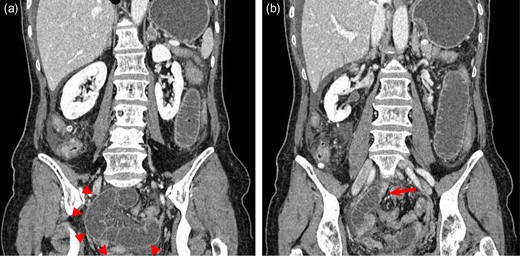

Computed tomography (CT) with contrast enhancement revealed a closed loop obstruction located in the pelvis (Fig. 2). In addition, the slightly decreased bowel wall enhancement of the closed loop and the moderate volume of ascites indicated bowel ischemia (Fig. 2). As these findings suggested small bowel strangulation due to an internal hernia, we performed an emergency exploratory laparoscopy.

(a) Contrast-enhanced coronal CT image showing a closed loop obstruction located in the pelvis (arrowheads), a slightly decreased bowel wall enhancement of the closed loop, and a moderate volume of ascites. (b) Another coronal slice of CT revealing the change in caliber (arrow) and a whirl sign.